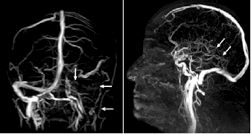

图2.左图示左静脉窦及颈静脉均无血流;

右图示深部静脉系统无血流(→)。

在看过患者影像学报告后告诉我们,刘同学所患脑梗的特殊之处在于,它并不是由于大脑动脉的梗塞,而是静脉脑梗。